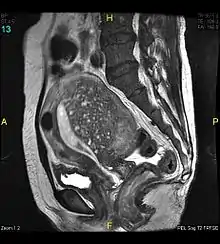

Magnetic resonance imaging

Magnetic resonance imaging (MRI) provides slightly better diagnostic capability compared to TVUS, due to the increased ability of MRI to differentiate objectively between different types of soft tissue.[24] This is possible with MRI's higher spatial and contrast resolution. Overall, it is estimated that MRI has a sensitivity of 74% and specificity of 91% for the detection of adenomyosis.[11] Diagnosis through MRI focuses predominately upon investigating the junctional zone. The uterus will have a thickened junctional zone with darker/diminished signal on both T1 and T2 weighted sequences.[24]

Three objective measures of the junctional zone can be used to diagnose adenomyosis.[24]

- A thickness of the junctional zone greater than 8–12 mm. Less than 8 mm is normal.

- A junctional zone width being greater than 40% of the width of the myometrium.

- Variability in the width of the junctional zone being greater than 5 mm.

Interspersed within the thickened, darker signal of the junctional zone, one will often see foci of hyperintensity (bright spots) on the T2 weighted scans representing small cystically dilatated glands or more acute sites of microhemorrhage.[24]

MRI is limited by other factors, but not by calcified uterine fibroids (as is ultrasound). In particular, MRI is better able to differentiate adenomyosis from multiple small uterine fibroids.